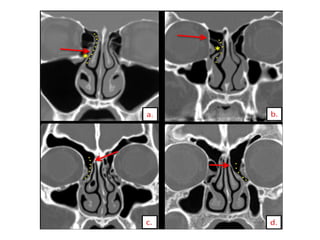

the right frontal recess(dotted red line), which is bounded anteriorly and laterally by an agger nasi cell (white arrow) and a type 1 frontal cell (black arrow), medially by the middle turbinate

posteriorly by the ethmoidbulla and bulla lamella. The nasofrontal process (arrowhead in b) forms the floor of the frontal sinus and demarcates the level of the frontal sinus ostium

Frontal outflow tractshows conglomeratization of air cells. Types of frontal sinus air cells include: • I – Type I frontal cell (a single air cell above agger nasi) • II – Type II frontal cell (a series of air cells above agger nasi but below the orbital roof) • III – Type III frontal cell (this cell extends into the frontal sinus but is contiguous with agger nasi • cell) • IV – Type IV frontal cell lies completely within the frontal sinus

Type 4 frontalcell situated entirely within the right frontal sinus & bordered by the anterior frontal sinus wall. The type 4 cell does not abut the agger nasi cell.

• #40 Type 2 frontal cells. (a, b) Coronal (a) and parasagittal (b) drawings show a tier of type 2 frontal cells (blue areas) sitting atop an agger nasi cell. (c, d) Coronal (c) and sagittal (d) CT images show a tier of two type 2 frontal cells (arrows) sitting directly atop an agger nasi cell (*).

• #41 Type 3 frontal cell. Coronal (a) and parasagittal (b) drawings show a type 3 frontal cell (blue area) sitting atop an agger nasi cell. The type 3 cell extends superiorly from the frontal recess through the frontal ostium and into the frontal sinus.

• #42  Type 4 frontal cell. (a, b) Coronal (a) and parasagittal (b) drawings show a type 4 frontal cell (blue area) situated entirely within the right frontal sinus and bordered by the anterior frontal sinus wall. The type 4 cell does not abut the agger nasi cell. (c, d) Coronal (c) and sagittal (d) CT images show an opacified type 4 frontal cell (arrow) in the frontal sinus.